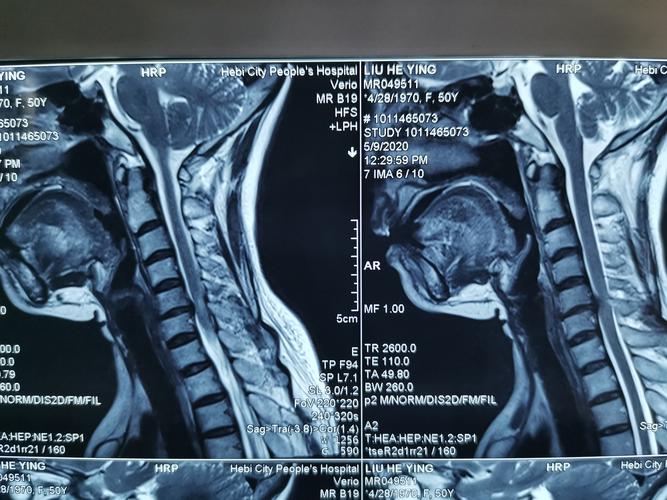

颈椎病核磁共振图解

颈椎病核磁共振图解,颈椎核磁片图解教程

颈椎核磁片图解教程

正常颈椎核磁共振图片

颈椎核磁共振图片图解

颈椎核磁共振

核磁共振图解

核磁共振图片

核磁共振片子

颈椎病片子